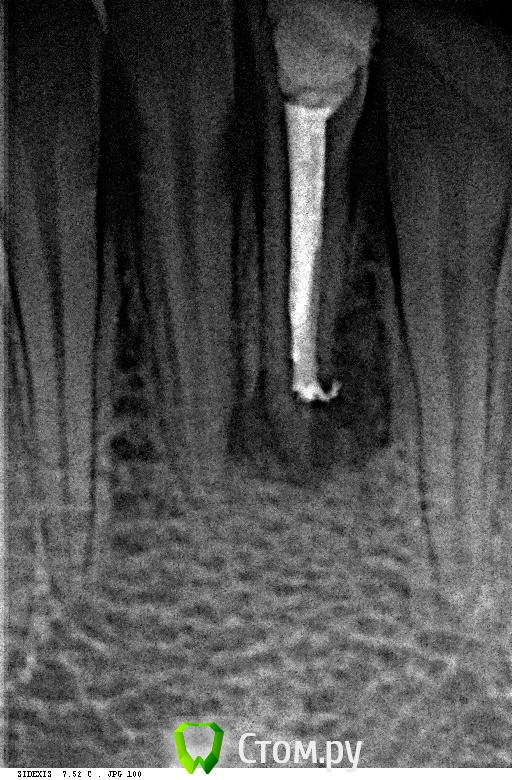

Alexandr Iv Опубликовано 29 июля, 2014 Поделиться Опубликовано 29 июля, 2014 Пациент Н. 14 лет.Диагноз: Хронический гранулирующий периодонтит зуба 3.1Зуб ранее дважды лечен эндодонтически. Корневой канал "обтурирован" проволокой. Был направлен на удаление. Хирург пригласил на консультацию. Решили "спасать". За час под микроскопом извлечена проволока (наверно, это проволока)) ) методом захвата в самодельный цилиндр (из носика для жидкотекучего) и заклиниваем проволоки в цилиндре с помощью 25 к-файла. Обработка и обтурация корневого канала. SoftCore + несколько дополнительных штифтов. Восстановление коронки зуба Filtek Ultimate. Каков на Ваш взгляд прогноз зуба и как Вы видите дальнейшее восстановление коронковой части? Ссылка на комментарий

Бобр Опубликовано 29 июля, 2014 Поделиться Опубликовано 29 июля, 2014 На мой взгляд прогноз не утешительный, слишком тонкие стенки у корня. Перфорации возможно и нет, но резорбция точно есть. Стоило наверное провести через кальций и обтурировать апекс мта 3 Ссылка на комментарий

Л Ю С Я Опубликовано 29 июля, 2014 Поделиться Опубликовано 29 июля, 2014 Прогноз неблагоприятный. Очень тонкие стенки корня, да и коронка прилично распахана. Есть риск фрактуры. Через 6 месяцев вызывайте на рентген. Я бы тоже обтурировала апекс мта. Радует только молодой возраст 1 Ссылка на комментарий